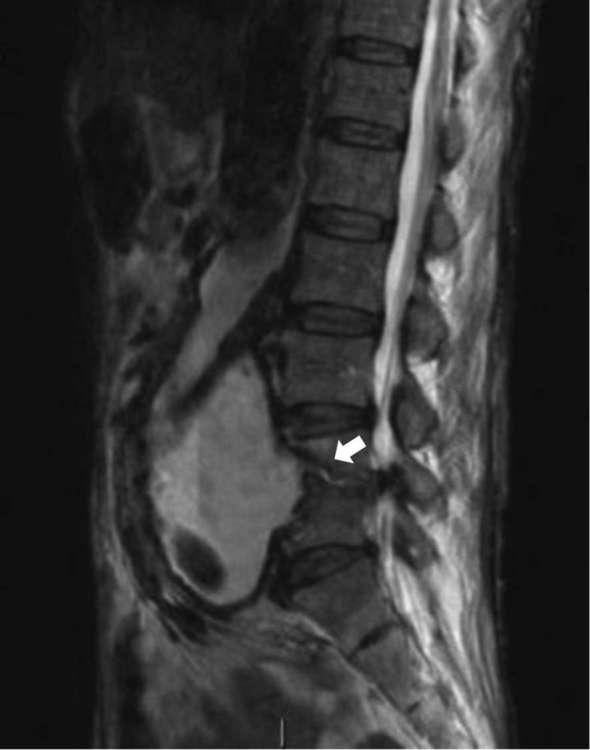

We present the case of a 68-year-old male, who underwent open abdominal aortic graft in August 2016 owing to a ruptured large infrarenal abdominal aneurysm. He subsequently presented 6 months later with back pain, general weakness, reduced mobility and cachexia. He underwent CT, MRI and fluorodeoxyglucose (PDG)-PET spinal imaging, all modalities showing signs of aortic graft infection complicated by L4/5 discitis. The patient was treated conservatively with intravenous antibiotics and spinal brace support, as his general condition did not allow for surgery. Although he showed initial clinical improvement allowing plans for supported discharge, his improvement was not sustained and he died 4 months after admission.